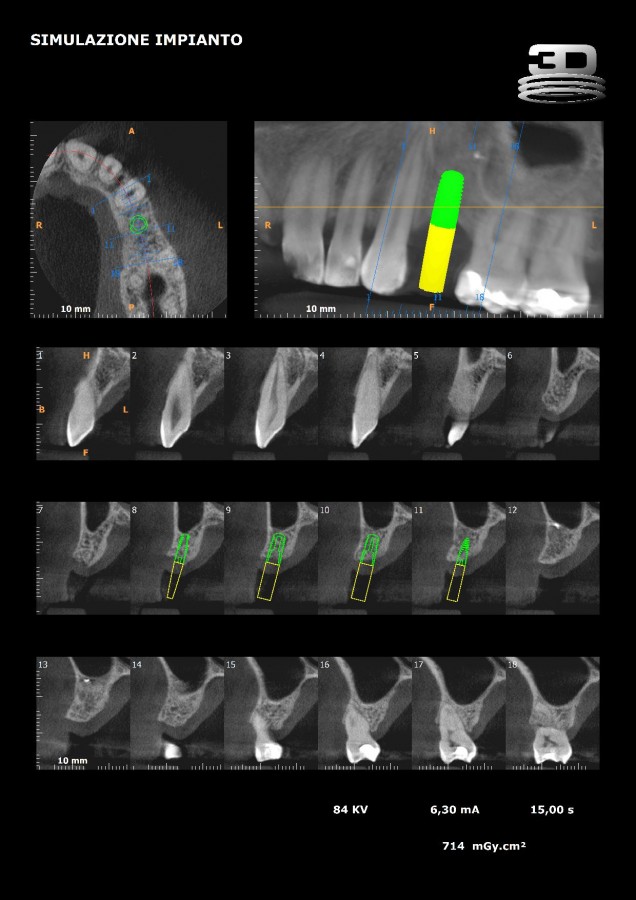

CASI CLINICI: